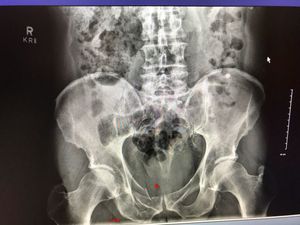

The patient in question is 73 years old and he fell mountain biking and landed directly on his pelvis.

Inferior and superior pubic ramus fracture ?

yep! 👩🏼‍⚕️

Acetabular fracture too?

Fx but is urin tract and bladder is preserve?

yes, but there is a small hematoma in the bladder as well.